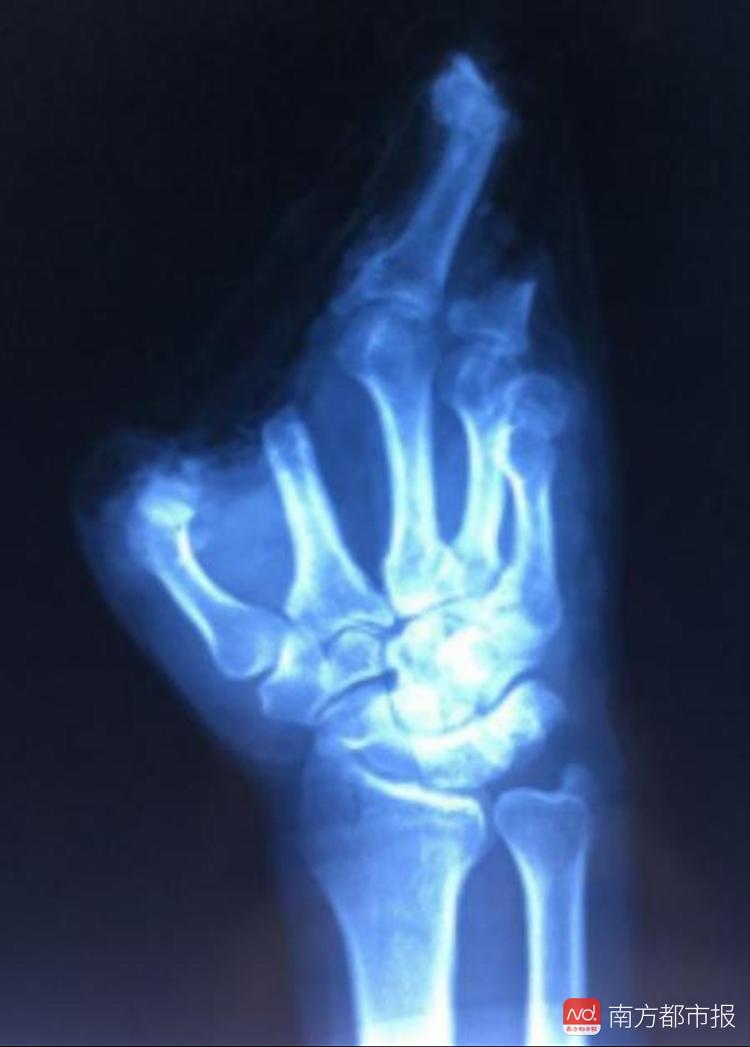

五个手指头和掌心断裂,这只手还有救吗?记者今日从深圳市二医院了解到,深圳一名建筑工人在工地意外受伤,导致右手五指完全撕脱离断,经过手足外科团队全体协作,连续昼夜奋战18个小时,五指全部再植成功。

手足外科的全体医生团结协作,昼夜奋战近18个小时,终于在第二天早上8点成功完成五指撕脱离断的再植手术。患者右手完全离断的五个伤指在离体10多个小时后被全部原位接回。看着患者安全送出手术室,连续忙碌了整整一天一夜的医生们几近虚脱。术后,患者和家属看着被成功接活的手指,对全体医护人员非常感谢。